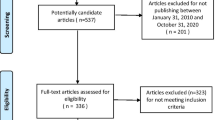

Between January 2012 and August 2013, 154 consecutive patients with suspected intracranial atherosclerotic diseases referred from Department of Neurosurgery, Changhai Hospital, Shanghai, China, were recruited. These patients presented with symptoms and signs of MCA territory ischemia or infarction either clinically or on the basis of neurological imaging, including T1-, T2-, diffusion-weighted (DWI), T2-fluid attenuated inversion recovery (FLAIR) brain imaging and/or whole brain computerised tomography perfusion (CTP) imaging. The study protocol was approved by the local institutional review board with all patients providing written informed consent.

Patients underwent hrMRI MCA imaging with inclusion criteria being: (1) absence of significant carotid arterial stenosis (<30 %) assessed by ultrasound; (2) absence of atrial fibrillation on 24 hr monitoring; (3) absence of ascending aortic arch atheroma on MR; and (4) ≥1 atherosclerotic risk-factors, including hypertension, diabetes mellitus, hypercholesterolemia or cigarette smoking. Exclusion criteria: (1) non-atherosclerotic intracranial arterial disease, e.g. inflammatory arteritis and congenital agenesis; (2) suspected cardio-embolic stroke; (3) known coagulopathy; (4) previous MCA stenting; or (5) clinical contraindications to MRI.

One hundred and nine volunteers referred by Health Examination Centre, Changhai Hospital, were also recruited consecutively as asymptomatic controls with inclusion criteria (1–4) and MCA blood flow velocities >160 cm/s [17] assessed by transcranial Doppler or no detectable Doppler shift. There was no upper limit to MCA flow velocity and hence, volunteers with moderate/severe stenosis were not excluded. Investigators screening volunteers were blinded to their clinical status.